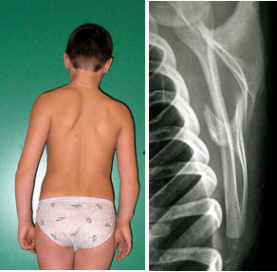

Consiste nel sollevamento del bordo vertebrale della scapola che si allontana dal piano del torace e diviene più sporgente. Può essere mono o bilaterale. In quest’ultimo caso la causa più frequente è un dorso curvo astenico (fig. 1), in cui si osserva un’accentuazione delle cifosi e della sottostante lordosi lombare, addome prominente con ipotonia degli addominali. La buona autocorreggibilità in posizione eretta e seduta, l’assenza di dolori e di rigidità orientano verso una forma “benigna” di dorso curvo, da trattare con attività sportive come nuoto e ginnastica, ma bisogna essere ben certi che non si tratti di una distrofia muscolare debuttante.